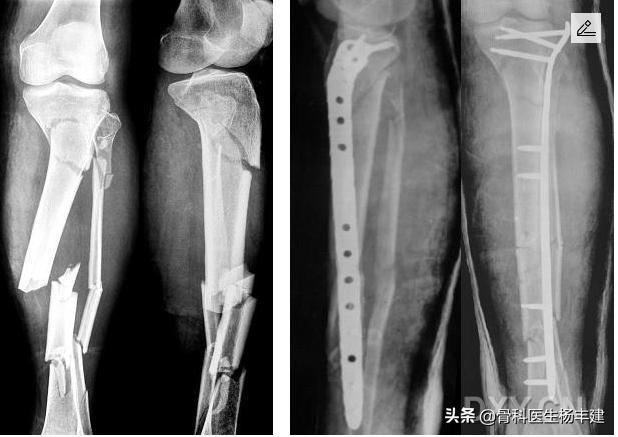

(2)钢板原理使用不当

根据骨折的不同形式,钢板的固定原理分为“加压固定”“桥接固定”“支撑固定”等等多种固定原理。对于长骨的粉碎性骨折,使用钢板时一定注意桥接固定原理原理,这种情况下螺丝钉的安排非常讲究。我们注意到,有些基层的医生在这一方面略微欠缺,有时候会做出不伦不类的固定来。充分理解这些原理,是骨科医生与木匠的区别。

桥接钢板往往用于复杂的粉碎性骨折,用好桥接板并不是简单事情